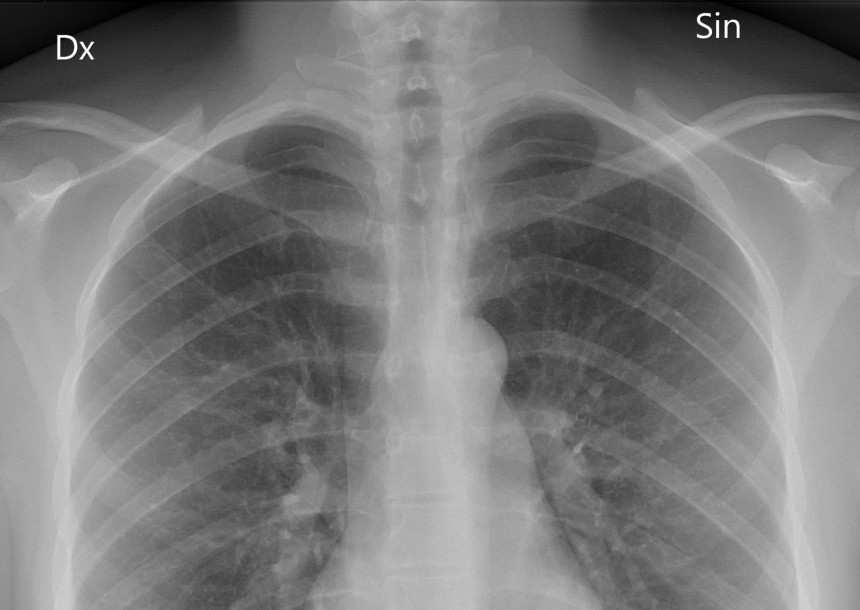

Speciālisti novērojuši satraucošu tendenci ‒ jauno diagnosticēto tuberkulozes gadījumu īpatsvars ir sarucis vidēji par 20 procentiem salīdzinājumā ar pagājušo gadu, tāpat pieaudzis to pacietu skaits, kuriem tuberkuloze tiek diagnosticēta jau smagā, ielaistā slimības formā. Speciālisti vērš uzmanību, ka šīs tendences varētu būt saistītas ar to, ka daļa tuberkulozes pacientu nemaz nav nonākuši līdz plaušu speciālistiem, lai saņemtu palīdzību, tāpat arī daļa pacientu vēršas pie speciālistiem novēloti, kad slimība ir smagi ielaista. Daļēji šādas izmaiņas varētu būt saistītas ar Covid-19 pandēmijas izraisīto ietekmi uz tuberkulozes kontroles un veselības aprūpes sistēmu.

Kā norāda Rīgas Austrumu slimnīcas Tuberkulozes un plaušu slimību centra galvenā ārste Andra Cīrule, datu par saslimstību ar tuberkulozi visā valstī mums nav, bet ir dati par saslimstību ar multirezistento tuberkulozi, ko apkopo slimnīca, un faktiski šie dati apliecina, ka šā gada desmit mēnešos pacientu skaits ir būtiski mazāks nekā 2019. gadā. Šogad multirezistenta tuberkuloze atklāta 22 pacientiem (iepriekšējos gados vismaz uz pusi vairāk). “Vai tā ir realitāte vai tomēr maldīgs skats uz tuberkulozes izplatību?” retoriski vaicā A. Cīrule. “Aktuāls ir jautājums, vai visi pacienti, kuriem ir sūdzības, nonāk pie ārstiem un vai tiek diagnosticēta tuberkuloze, ņemot vērā Covid-19 izplatību? Saslimstība ar tuberkulozi pieaug ekonomiskās un sociālās krīzes apstākļos, mēs domājam, ka pašlaik ir šāda krīze un mums ir jābūt gataviem tuberkulozes uzliesmojumam.”

Tuberkulozes un plaušu slimību centra Multirezistentās tuberkulozes nodaļas vadītāja, PVO sadarbības centra vadītāja Līga Kukša norāda, ka viens no iemesliem ir sabiedrības noskaņojums ‒ pacienti domā, ka viņus nepieņems un neiet pie ārsta. “Veselības pakalpojumu ierobežošana bija tikai pavasarī, un daļa pacientu patiešām neatnāca vai kavējās nākt šī iemesla dēļ, tomēr jāatceras, ka ar tuberkulozi slimo dažādas pacientu grupas - daļa aktīvi iet uz izmeklējumiem un ārstējas, bet daļa ir tādi pacienti, kuri jāmeklē un jāuzrauga ārstēšanās procesā,” saka L. Kukša. Ārsti ir ļoti nobažījušies par situāciju, jo slimnīcā parādās jau pacienti galējā stāvoklī, kuri laikus nav izmeklēti un ārstējušies. Šogad reģistrēti 14 nāves gadījumi, kad pacieti pēc ievietošanas slimnīcā nomiruši ļoti ātri, un tas nozīmē, ka diagnoze ir uzstādīta stipri novēloti.